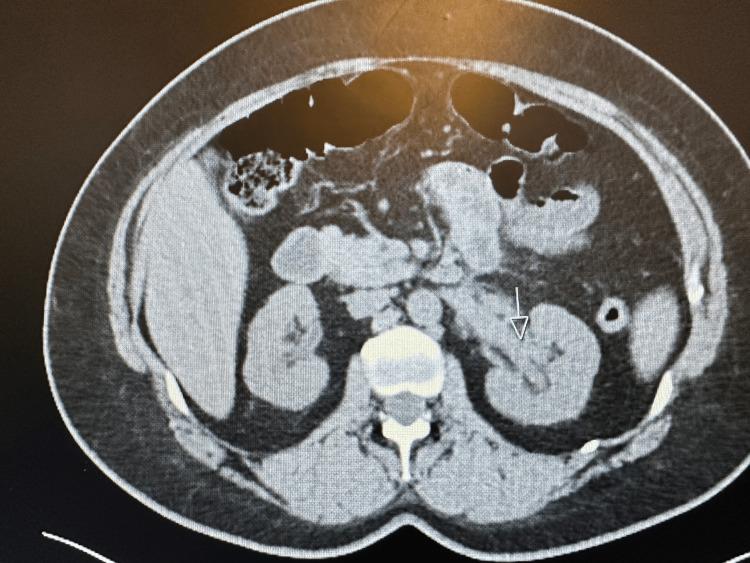

Interstitial granulomatous dermatitis (IGD) is a rare dermatological disorder. It is most commonly associated with autoimmune disorders mainly lupus and rheumatoid arthritis. It has rarely been reported to present as a first manifestation of an underlying vasculitis. Here, we present a case of a 44-year-old woman who presented initially with a violaceous rash starting in her neck and trunk and extending to her limbs, but sparing the palms and soles. She was also found to have an acute kidney injury. A biopsy of the skin lesion confirmed the diagnosis of IGD, and a kidney biopsy showed findings consistent with granulomatosis with polyangiitis. To the best of our knowledge, this is the seventh reported case of IGD associated with systemic vasculitis.

间质性肉芽肿性皮炎(IGD)是一种罕见的皮肤病。它最常与自身免疫性疾病相关,主要是狼疮和类风湿性关节炎。很少有报道称它是潜在血管炎的首发表现。在此,我们报告一例44岁女性病例,该患者最初表现为颈部和躯干出现紫红色皮疹,并蔓延至四肢,但手掌和脚底未受累。她还被发现患有急性肾损伤。皮肤病变活检确诊为IGD,肾脏活检结果与肉芽肿性多血管炎一致。据我们所知,这是第七例报道的与系统性血管炎相关的IGD病例。